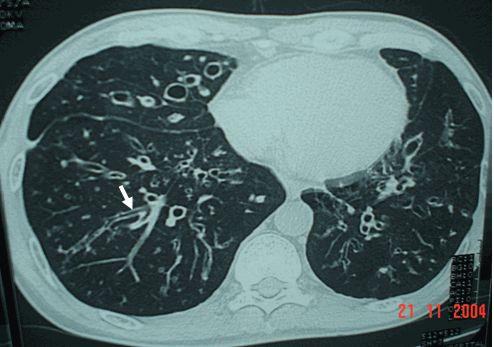

Giãn phế quản phổi phải dạng chùm nho

- Hình túi hoặc nang: giãn phế quản dạng cụm nang. Đây là hình thức nghiêm trọng nhất của giãn phế quản và thường được tìm thấy ở những bệnh nhân bị xơ nang.

Đường hô hấp bị ảnh hưởng đang viêm và dễ dàng suy yếu. Có sự giảm luồng không khí và thoát chất tiết, dẫn đến sự tích tụ số lượng lớn các chất nhầy trong phổi. Chất nhầy thu thập vi khuẩn, nguyên nhân nền để nhiễm trùng đường hô hấp dưới thường xuyên và thường nặng. Mức độ nghiêm trọng của chứng giãn phế quản thường được phân loại theo khối lượng đờm nhưng nay phần lớn được thay thế bằng sự xuất hiện dấu hiệu trên CT scan.